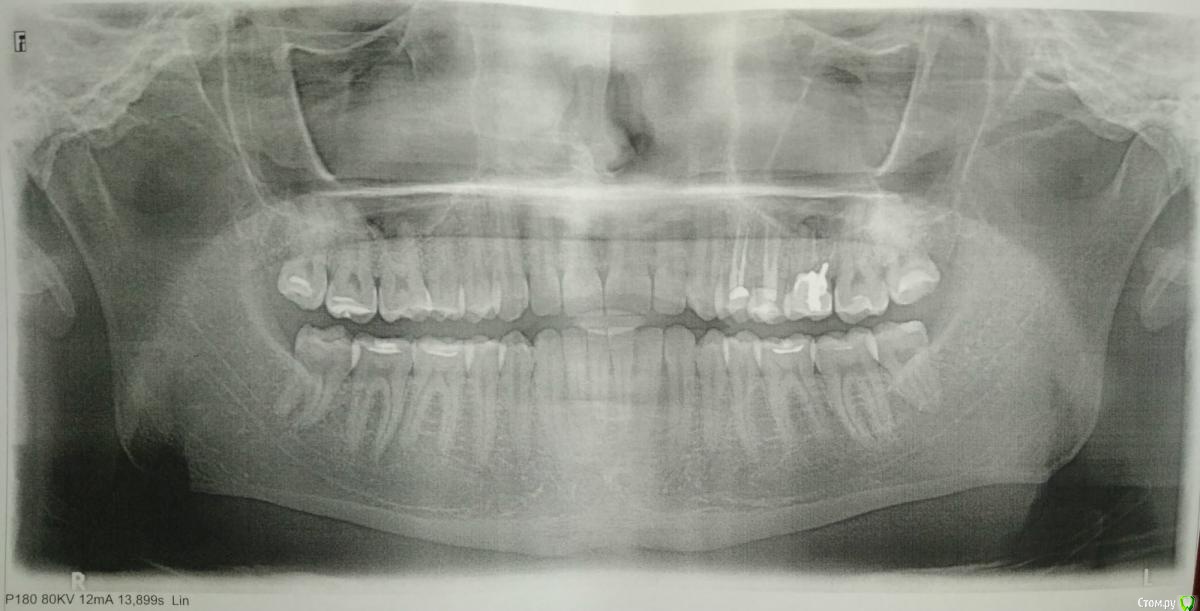

первый раз сделали панорамный снимок, вскрылась проблема.

со слов стоматолога: зуб шестёрка (на снимке сверху справа) - стоит непонятная полу-коронка со штифтом, каналы не были заделаны (правильно?), рассасывание костной ткани, хроническое воспаление, рядом пазуха и есть щели с соседними зубами 5, 7.

Её рекомендация -

1) удалить поскорее, далее заживление 3-.. месяцев и имплант,

2) имплант с коронкой на этот и два соседних зуба (5,4) - потому что пломбы, судя по снимку, глубокие.

от меня: щели 6-5 6-7 беспокоят, постоянно забивается пища, потемнение эмали там.